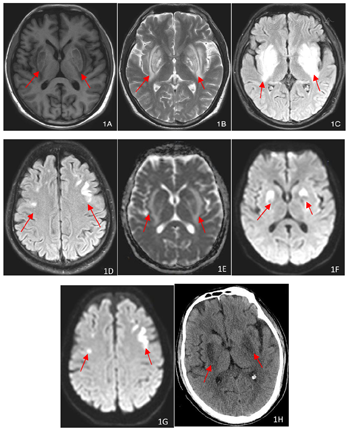

外院相关检查:2022年7月14日血气:pH 7.17,二氧化碳分压(PaCO2)21 mmHg,氧分压(PaO2)159 mmHg,钠133 mmol/L,葡萄糖6.8 mmol/L,乳酸17 mmol/L,实际碳酸氢根7.7 mmol/L,标准碳酸氢根10.1 mmol/L。肾功能:肌酐1107 μmol/L,尿素氮20.2 mmol/L。2022年7月14日头颅CT:两侧基底节区对称性密度减低。2022年7月19日头颅MR+增强:双侧额叶及基底节见斑片状,小片状稍长T1稍长T2信号影,增强强化不明显,弥散像呈高信号,ADC呈低信号,周围可见水肿信号,考虑代谢性脑病,结合临床考虑肾性脑病可能。入住我院相关化验,2022年7月31日血气分析,pH 7.45,二氧化碳分压31.1 mmHg,氧分压149.8 mmHg,实际碳酸氢根21.4 mmol/L,标准碳酸氢根22.7 mmol/L,阴离子间隙20.5,乳酸0.6 mmol/L,钾3.84 mmol/L,钠138.5 mmol/L,钙1.23 mmol/L。2022年7月31日血常规:白细胞9.3×109/L,中性粒细胞占比0.787,红细胞计数2.58×1012/L,血红蛋白83 g/L,血小板计数230×109/L,2022年8月1日生化:白蛋白34 g/L,总胆红素3.9 μmol/L,谷丙转氨酶3 U/L,尿素氮35.48 mmol/L,肌酐645 μmol/L,尿酸488 μmol/L。尿常规:尿蛋白阳性1+,尿隐血阳性3+,红细胞计数131/μl;甲状旁腺激素214.9 pg/ml。2022年8月5日腹透液常规:有核细胞计数10×106/L,蛋白定性2+;血钠125.9 mmol/L;2022年8月13日24 h尿钠328.6 mmol/24h,24 h尿量2900 ml。2022年8月15甲状腺功能:FT3 1.36 pg/ml,FT4 0.68 ng/dl。影像学检查:2022年8月2日胸部+腹部CT:两肺下叶微小结节,胆囊结石,胰头周围多发钙化灶,两肾多发囊性灶,左肾小结石。2022年8月2日头颅MR:两侧基底节、额叶异常信号,结合临床考虑尿毒症脑病,两侧额部硬膜下积液,两侧乳突炎,两侧上颌窦囊肿。2022年8月23日头颅MR:两侧基底节、额叶异常信号,符合尿毒症脑病,较前(2022年8月2日)吸收。发病第20天头颅MRI及CT表现见图1,发病第41天头颅MRI表现见图2。

患者入院时嗜睡,住院期间出现双手持续震颤加重,持物时明显,进食时有下颌及舌部抖动,咀嚼及吞咽困难,四肢肌力下降,下肢最低至0级,尿量最多达4400 ml,经上述治疗患者神志转清,震颤消失,口齿逐渐清楚,四肢肌力恢复至正常,复查头颅MRI提示病灶明显吸收,住院第32天顺利出院。

豆状核叉征是一种特征性的影像学表现,可视为尿毒症脑病的基底神经型,在CT上表现为双侧豆状核区对称性低密度改变,在头颅MRI上为双侧豆状核区对称性T1WI像低信号,T2WI像及T2FLAIR像高信号,这种高信号尤以豆状核边缘的内囊后肢及外囊最为明显,且两者向后延伸形成叉状外观,叉子的柄由内囊后肢和外囊后部融合而成,内囊后肢和外囊分别构成叉子的内侧臂和外侧臂,内外两臂之间夹着豆状核(包括壳核及内外侧苍白球)[1]。